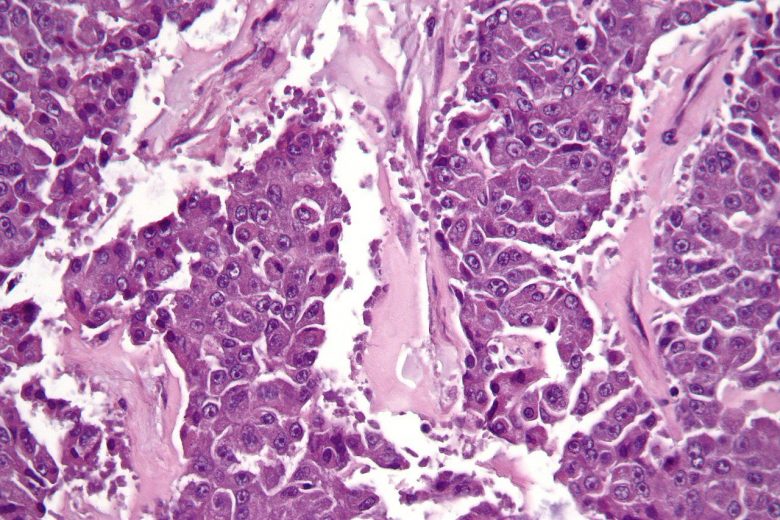

Pancreatic cancer

“Pancreatic cancer can develop from two kinds of cells in the pancreas: exocrine cells and neuroendocrine cells, such as islet cells. The exocrine type is more common and is usually found at an advanced stage. Pancreatic neuroendocrine tumors (islet cell tumors) are less common but have a better prognosis.”

Important facts about pancreatic cancer:

Image Credit: Nephron / Wikimedia Commons.